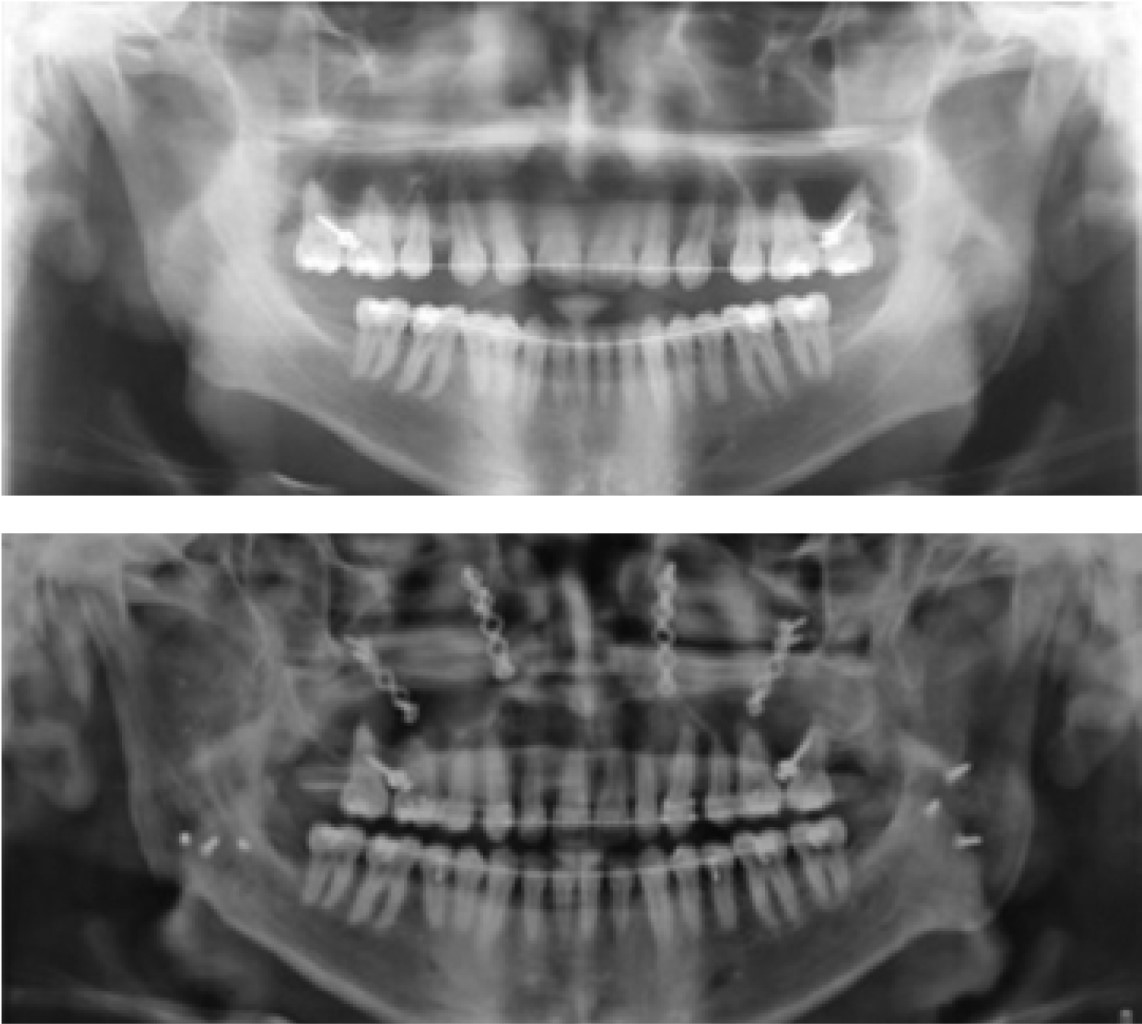

En la cefalometría de Steiner se identifica ángulo SNA de 83o, ángulo SNB de 90o y ángulo ANB de 8o (Figura 4).

Figura 4

Figura 5

Figura 6